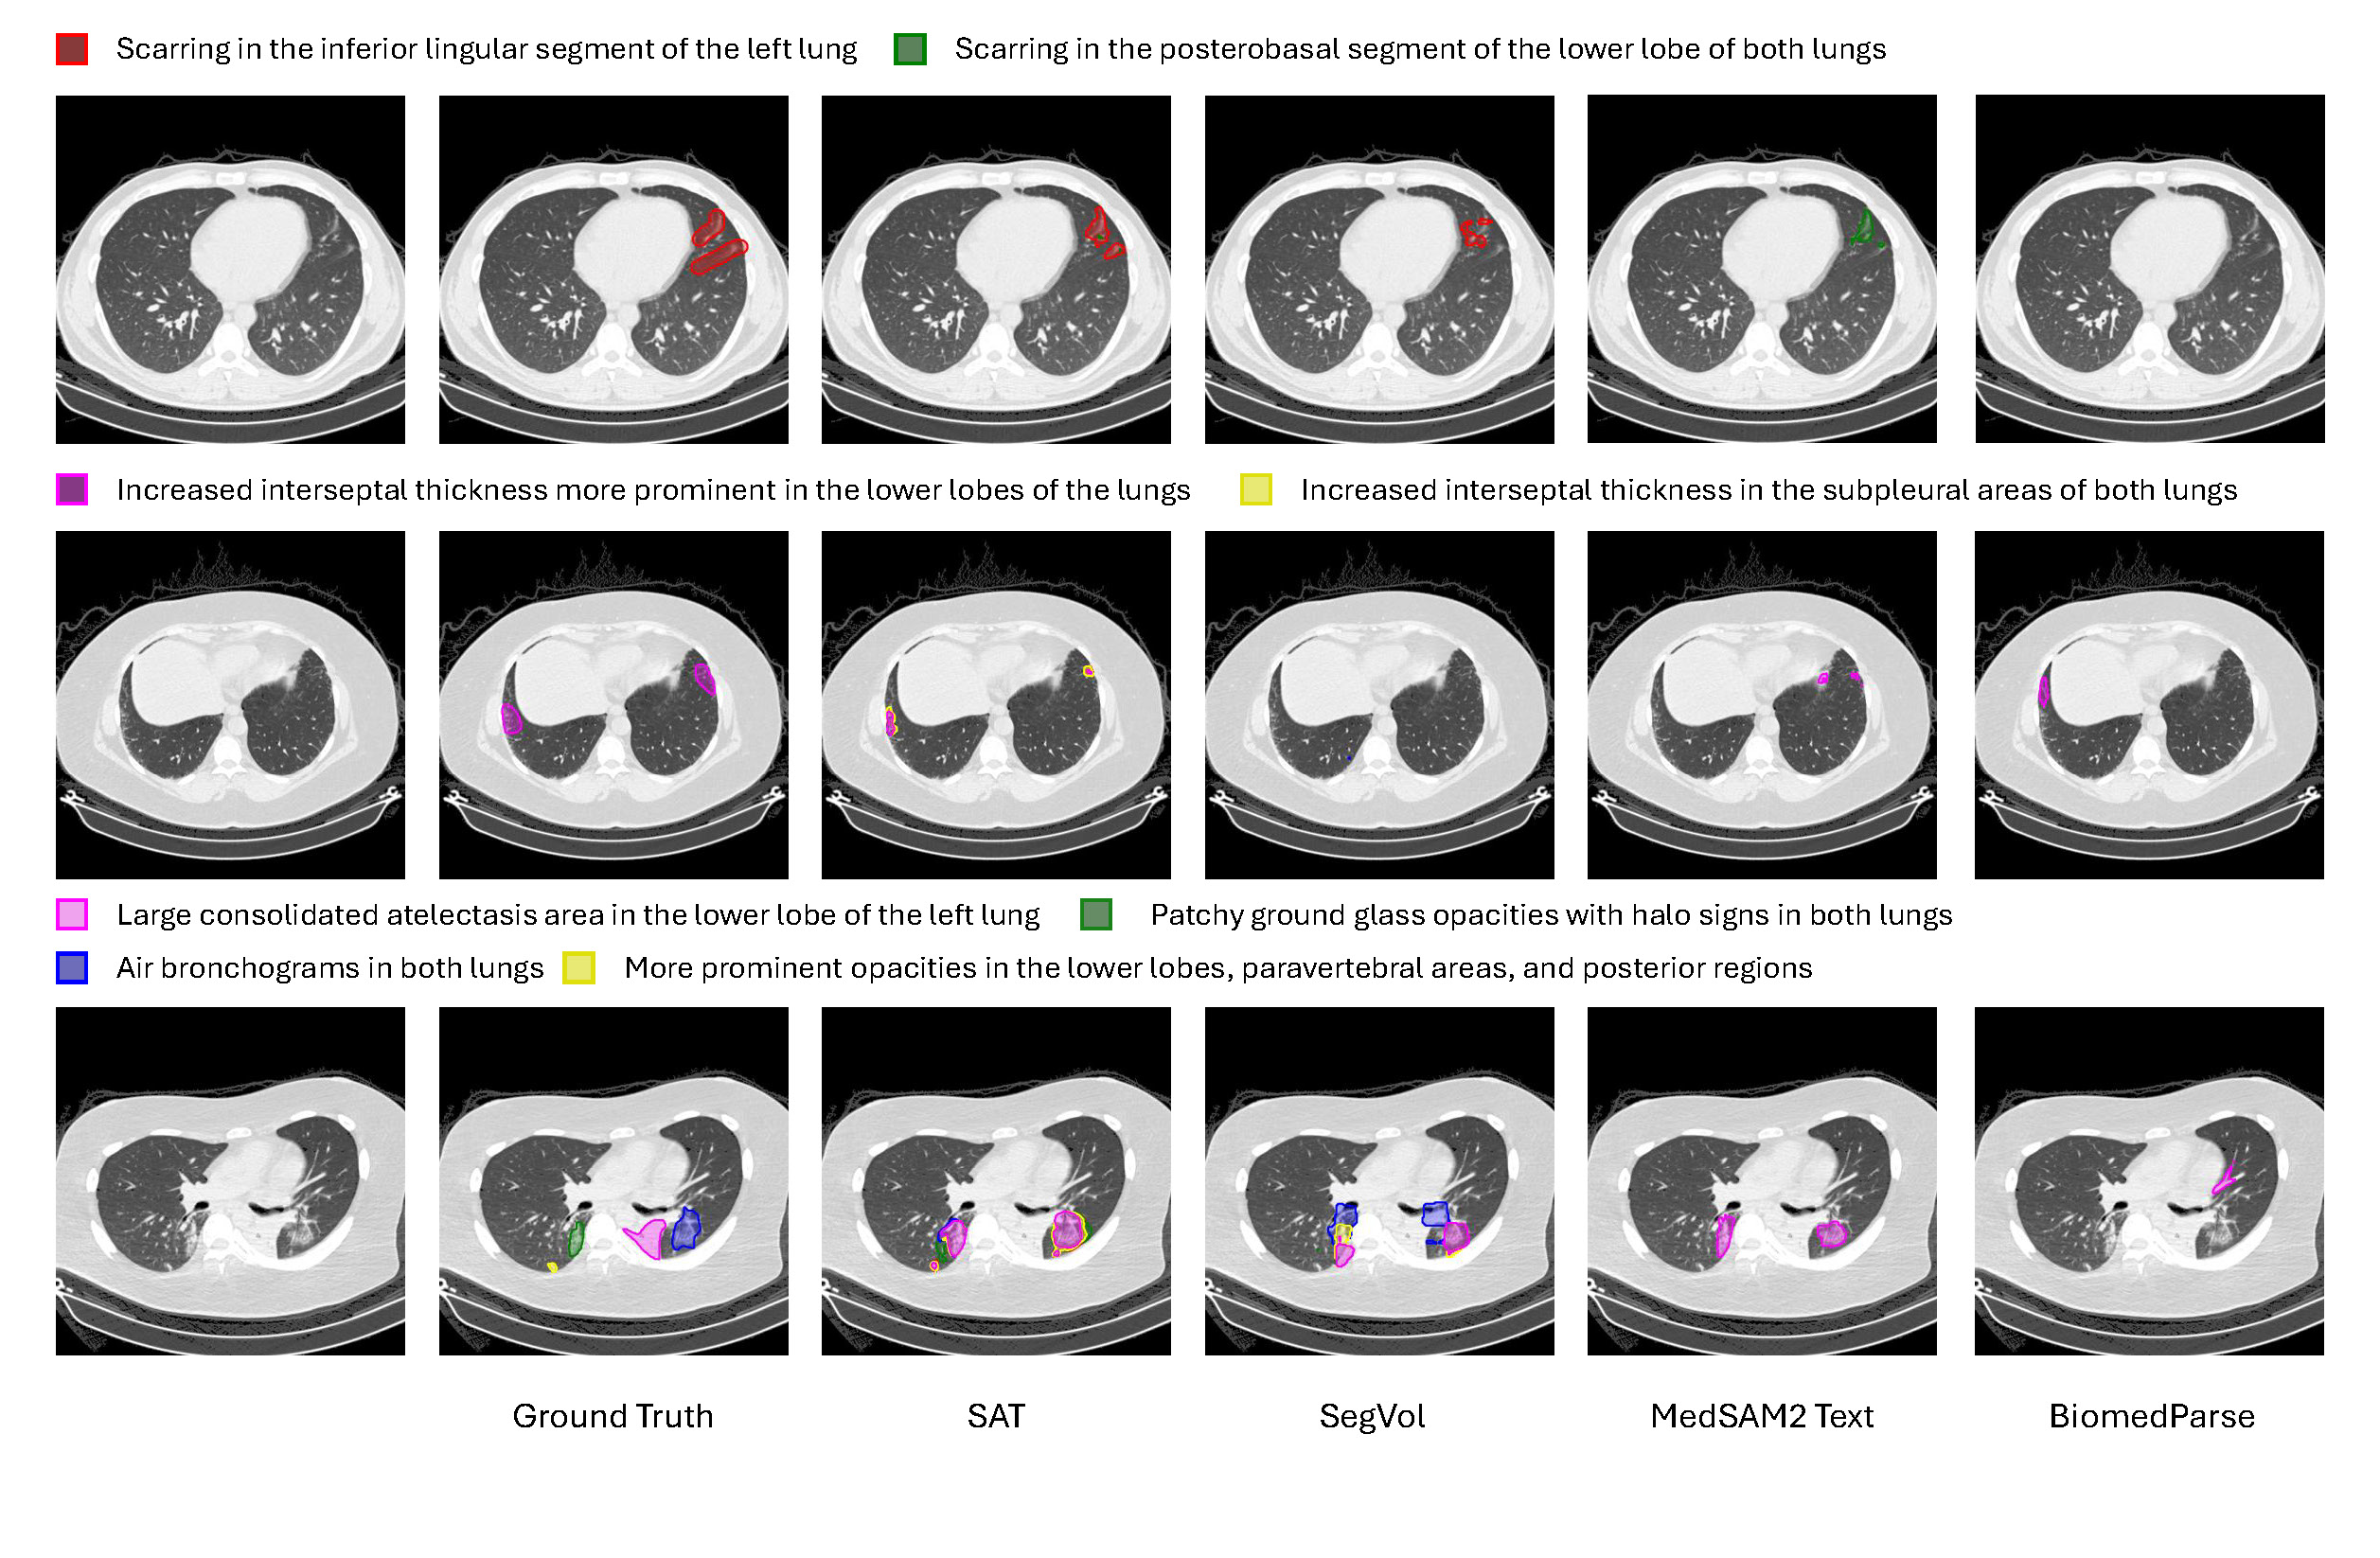

State-of-the-Art Text-prompted Medical Segmentation Models Struggle to Ground Chest CT Findings

Mohammed Baharoon, Luyang Luo*, Michael Moritz, Abhinav Kumar, Sung Eun Kim, Xiaoman Zhang, Miao Zhu, Kent Kleinschmidt, Sri Sai Dinesh Jaliparthi, Sathvik Suryadevara, Rithvik Akula, Mark Marino, Wenhui Lei, Ibrahim Ethem Hamamci, Pranav Rajpurkar

Machine Learning for Healthcare (MLHC), 2025

ReXGroundingCT

ReXGroundingCT: A 3D Chest CT Dataset for Segmentation of Findings from Free-Text Reports

Mohammed Baharoon*, Luyang Luo*, Michael Moritz, Abhinav Kumar, Sung Eun Kim, Xiaoman Zhang, Miao Zhu, Mahmoud Hussain Alabbad, Maha Sbayel Alhazmi, Neel P. Mistry, Kent Ryan Kleinschmidt, Brady Chrisler, Sathvik Suryadevara, Sri Sai Dinesh Jaliparthi, Noah Michael Prudlo, Mark David Marino, Jeremy Palacio, Rithvik Akula, Hong-Yu Zhou, Ibrahim Ethem Hamamci, Scott J. Adams, Hassan Rayhan AlOmaish, Pranav Rajpurkar

NEJM AI, 2026, in press